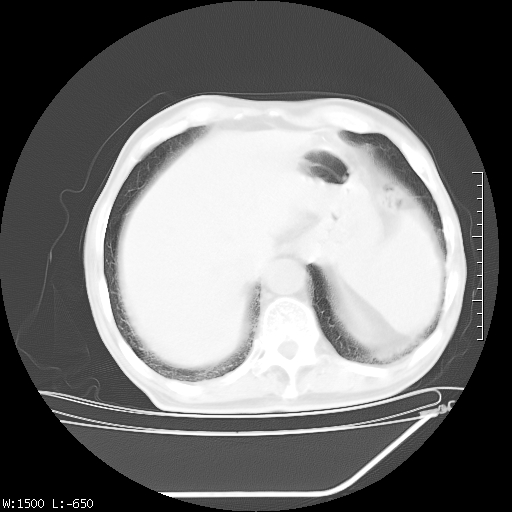

标题: CT23994:男、72、咳嗽、气短两月余,近来消瘦。 [打印本页]

标题: CT23994:男、72、咳嗽、气短两月余,近来消瘦。

右上肺大片状密度增高影,与胸膜关系密切,内见低密度透亮影,胸膜下可见三角形不张影,左下肺沿支气管走形结节影,纵膈内淋巴结显示。考虑结核并疤痕性不张可能性大,建议穿刺活检,排除肺泡癌。